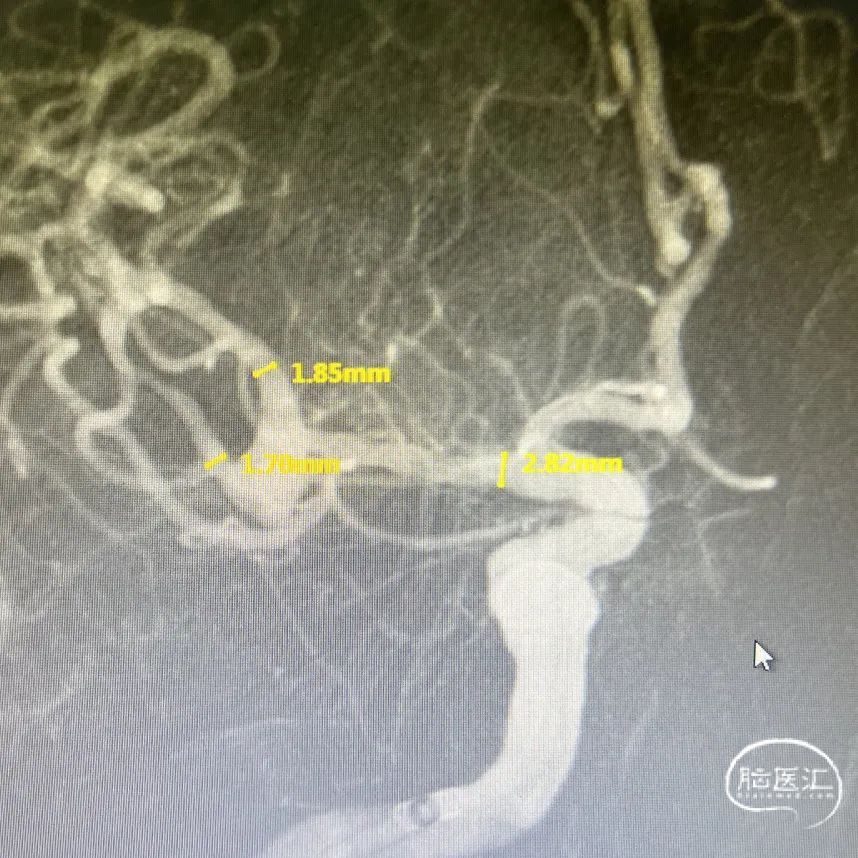

DSA:右侧大脑中动脉分叉部动脉瘤,约3*5mm,颈宽约5mm,伴上下干起始部扩张。

大脑中动脉近端M1直径2.82mm,远端1.83mm,上干1.85mm,下干1.7mm。